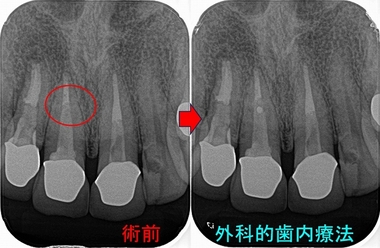

外科を開始すると

フィステルの原因は問題無いように見えた右上1の唇側の側枝(神経管の横枝)

側枝を削った所

病変があった為か側枝周りの部分がクレーター状に少し凹んでいました。

CTをよくよく見返すと、「えっ!?これ!?」という自分では診断が付けれなかった部位

CTは時間のある限り色々な方向で見るべきだなと痛感

側枝(凹んだ部分)を削りMTAを逆根管充填

側枝は根尖3mmに沢山出てくるとは言われていますが、まさかこの場所の側枝に細菌感染していたとは・・・